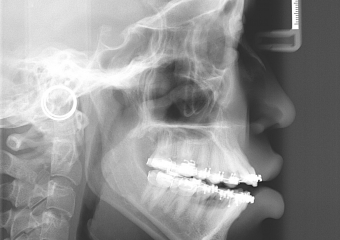

Telerradiografia após a cirurgia - Clínica Cliniface

Telerradiografia após a cirurgia